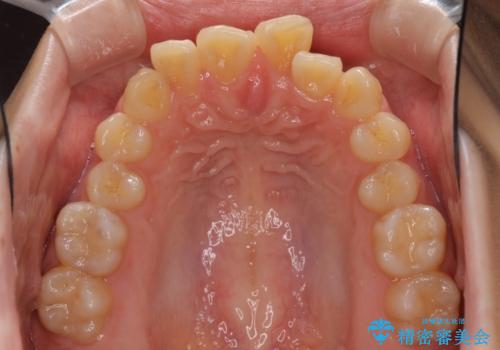

デコボコで飛び出した前歯をきれいに インビザラインによる矯正治療

- デコボコと飛び出した前歯を治したいとのことで来院された患者様です。

ゴムかけを活用して上顎歯列全体を後方移動し、IPR(歯と歯の間を削る)によってデコボコが解消するように設計し、インビザラインにより治療を行うこととしました。

毎日しっかりと装着してくださったので、概ねシミュレーション通りに歯を移動させることができました。

治療前には接触することのなかった上下の前歯が接触するようになり、食事の際前歯でものをかみ切れるようになりました。

気にしていた口元の印象が改善され、患者様には大変満足していただきました。